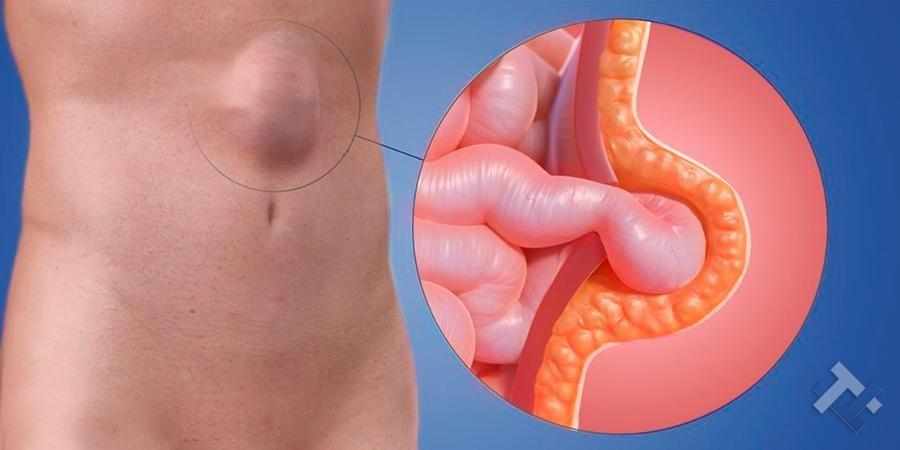

Ο Γενικός Χειρουργός Λιάγκος Γεώργιος MD PhD εκτελεί τις επεμβάσεις Λαπαροσκοπικά, Ενδοσκοπικά, Ανοιχτά Ελάχιστα Επεμβατικά και με Laser. Η θεραπεία εξατομικεύεται σε κάθε ασθενή ανάλογα με τις ανάγκες του. Αναλαμβάνει περιπτώσεις όπως κήλες και κοιλιοκήλες (αντιμετώπιση βουβωνοκήλης, αντιμετώπιση ομφαλοκήλης, θεραπεία επιγαστρικής κήλης, κήλη των αθλητών (Σύνδρομο κοιλιακών προσαγωγών), αντιμετώπιση μετεγχειρητικής κήλης, θεραπεία Μηροκήλης), πέτρες στη χοληδόχο κύστη, λαπαροσκοπική χολοκυστεκτομή, αντιμετώπιση Κύστη Κόκκυγος με λέιζερ (laser), παθήσεις πρωκτού, χειρουργική laser σύγχρονων κυκλικών ινών (αιμορροΐδες αντιμετώπιση, θεραπεία αιμορροϊδων με laser (LHP), αφαίρεση αιμορροΐδων με υπερήχους (HALL-RAR), χωρίς Χειρουργείο με ελαστικούς δακτυλίους (Τεχνική BARON-RBL), θεραπεία ραγάδας πρωκτού (Ραγάδα δακτυλίου), θεραπεία περιεδρικού συριγγίου, θεραπεία περιεδρικού αποστήματος, κονδυλώματα πρωκτού Θεραπεία, δερματικό ράκος (Skin tag) εκτομή, αντιμετώπιση Kνησμού, καρκίνος πρωκτού θεραπεία), παθήσεις Δέρματος, χειρουργική με laser CO2, αφαίρεση μορφωμάτων δέρματος - βιοψίες, αφαίρεση ελιάς (Σπίλου), σμηγματογόνος κύστης θεραπεία, αφαίρεση λιπώματος, είσφρυση όνυχος χειρουργείο, καρκίνος δέρματος θεραπεία, οξεία σκωληκοειδίτιδα, παθήσεις Λεπτού και Παχέος Εντέρου, ειλεός λεπτού εντέρου, εκκολπωμάτωση (Εκκολπωματίτιδα) σιγμοειδούς, καρκίνος παχέος εντέου, κολοστομίες, port χημειοθεραπείας κ.α. εξυπηρετώντας Παγκράτι και γύρω περιοχές.